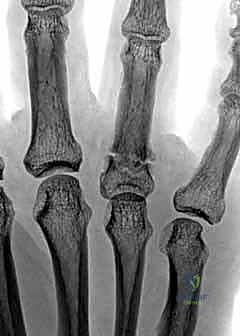

- التصوير بالأشعة السينية (X-rays): هو المعيار الذهبي لتشخيص كسور السلاميات. يطلب الدكتور هطيف دائماً ثلاث وضعيات أساسية:

- الأمامية الخلفية (AP View).

- الجانبية الحقيقية (True Lateral View): وهي الأهم لتقييم مقدار الانزياح الزاوي.

- المائلة (Oblique View): تساعد في رؤية الكسور الشعرية الدقيقة أو الكسور المفصلية الخفية.